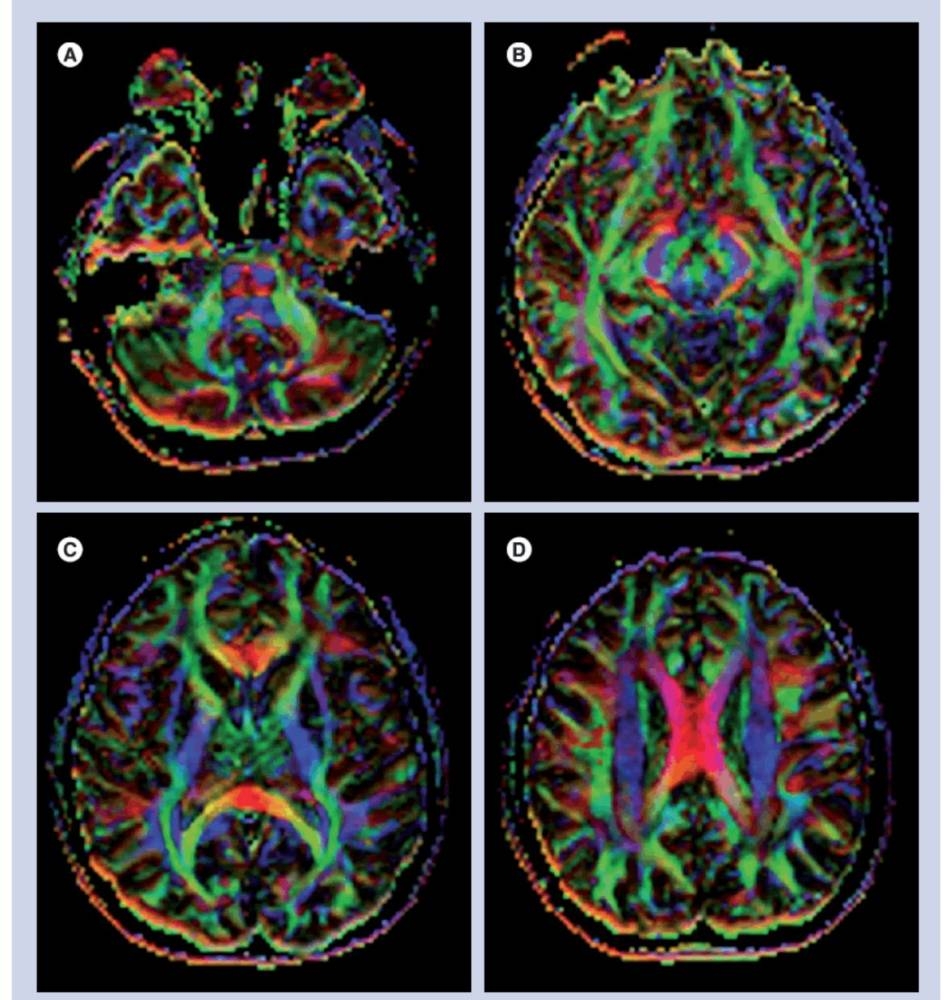

كما كشفت صور الدماغ تغيّرات في النشاط العصبي داخل مناطق مسؤولة عن الحركة والتوازن، مثل الفص الجبهي والمخيخ. ورغم أن المشاركين لم تظهر عليهم أعراض واضحة مثل الدوار أو التشويش الذهني، إلا أن الباحثين اعتبروا ما حدث بمثابة «تأثير صامت» قد يتراكم على مدى السنوات.